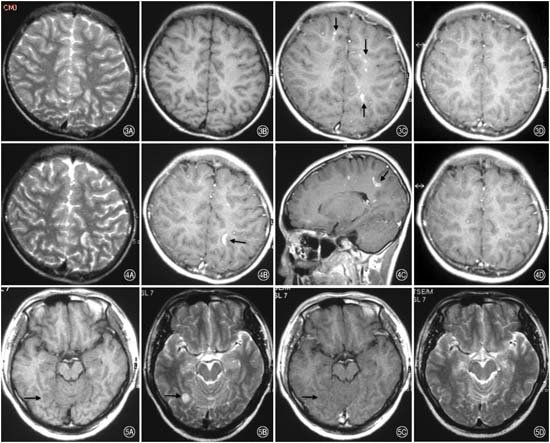

Một bệnh nhân nam 44 tuổi hoàn toàn khỏe mạnh trước đó biểu hiện đau cơ, dị cảm và nhức đầu tiến triển. Triệu chứng của anh ta bắt đầu sau 5 tuần kể từ khi đi nghỉ ở vùng Nam Thái Bình Dương ở trở về và ở đó anh ta đã ăn hải sản, uống nước trong dòng chảy ao hồ, sông, suối và phơi nhiễm nhiều loại côn trùng và dơi. Ba ngày sau khi trở về Mỹ, anh ta bị sốt (38.9°C) và có hội chứng viêm hô hấp trên. Tiếp đến anh ta đau cả toàn thân minh và bệnh lý thần kinh các chi. Công thức máu đáng chú ý là có bạch cầu ái toan tăng cao nên được khuyên nhập viện. Tại thời điểm nhập viện, bệnh nhân có biểu hiện nhức đầu nặng và cảm giác sợ ánh sáng nặng. Công thức máu toàn phần đáng chú ý có dấu nhiễm trùng với chỉ số bạch cầu 12.2 cells/µL với 9% eosinophils. Tốc độ máu lắng là bình thường và chỉ số C-reactive protein trong giới hạn. Chọc dò tủy sống cho thấy lực bình thường, bạch cầu là 55 cells/µL (với 96% lymphocytes), mức glucose là 54 mg/dL và protein là 97mg/dL. Chụp MRI vùng tủy sống và đầu cho thấy kết quả bình thường. Bệnh nhân được điều trị theo kinh nghiệm với thuốc ceftriaxone và acyclovir. Vì dấu chứng đau đầu ngày càng nặng hơn và có dấu hiệu dị cảm nặng di chuyển, nên tiếp tục chọc dò tủy sống một lần nữa vào ngày thứ 7 sau khi nhập viện cho thấy áp lực nước mở 49 mm (bình thường < 21cm nước) và chỉ số bạch cầu chung là 754 cells/µL, với phân tích công thức bạch cầu là 44% neutrophils, 35% lymphocytes, 10% plasma cells và 11% monocytes. Đánh giá lại phiến máu dịch não tủy cho thấy bạch cầu ái toan gia tăng 44% không có đa nhân trung tính. Chụp lại MRI lần nữa cho thấy kết quả bình thường, khám đáy mắt cho biết phù gai thị bên trái. Do thông số bạch cầu ái toan trong dịch não tủy và máu ngoại vi tăng cao cùng với tiền sử có đi du lịch, nên bệnh nhân được chẩn đoán lại là viêm não màng não di giun sán (helminthic meningoencephalitis).

Việc chẩn đoán bệnh giun angiostrongyliasis dựa vào phần lớn tiền sử phơi nhiễm trước đó, đặc điểm lâm sàng và tăng BCAT trong dịch não tủy. Tăng BCAT trong máu ngoại vi có thể hiển thị. Các chỉ điểm cận lâm sàng của DNT về bệnh angiostrongyliasis gồm có dịch có vẩn đục, đám mây, áp lực mở tăng, protein tăng, nồng độ glucose bình thường và tăng số bạch cầu tuyệt đối với số BCAT tăng cao so với bình thường. Bệnh angiostrongyliasis thường không để lại các tổn thương tại chỗ qua hình ảnh CT hoặc MRI não bộ. Mặc dù, bệnh angiostrongyliasis thường có triệu chứng tự giới hạn, việc lựa chọn điều trị bao gồm can thiệp giảm triệu chứng hoặc phối hợp nhiều liệu pháp khác nhau. Điều trị triệu chứng bao gồm chọc lấy DNT xét nghiệm trước sau khi điều trị, làm giảm nhẹ bớt tình trạng tăng áp lực sọ não và thuốc giảm đau. Trong một nghiên cứu tiến cứu, Punyagupta và cộng sự đã tìm thấy một giải pháp giảm đau đầu trên 60% số ca chỉ bằng thuốc giảm đau đơn thuần ở các bệnh nhân có chẩn đoán lâm sàng VMNTBCAT. Vì tính nghiêm trọng của bệnh angiostrongyliasis được xem là thứ phát đối với phản ứng viêm trên vật chủ, nên thuốc steroids đã được nghiên cứu như một liệu pháp trị liệu tiềm năng. Lợi điểm của steroids là làm giảm nhẹ nhức đầu cũng đã minh chứng trong một nghiên cứu tiến cứu VMNTBCAT lâm sàng điều trị với prednisone qua thời gian 2 tuần. Một số nghiên cứu chưa tìm thấy rằng thuốc steroids có thể hỗ trợ trong điều trị nhiễm trùng do Angiostrongylus.

Chẩn đoán bệnh do ấu trùng giun đầu gai là môt thách thức. Sự tăng BCAT trong máu ngoại vi và trong DNT kèm với tiến sử du lịch đến các vùng có nguy cơ nhiễm cao và diễn tiến các triệu chứng sẽ giúp hỗ trợ cho chẩn đoán bệnh này. Tuy nhiên, sự vắng mặt dấu tăng BCAT đã được báo cáo trong một số ít bệnh nhân nhiễm G. spinigerum. Phân tích mẫu bệnh phẩm DNT từ các bệnh nhân nhiễm ấu trùng giun đầu gai thường cho thấy có nhiễm sắc vàng, một dấu hiệu tăng áp lực sọnão trong khoảng 50% số bệnh nhân, tăng lumpho bào kèm theo tăng BCAT, nồng độ glucose bình thường và protein có thể bình thường hoặc tăng. Chụp CT-scanner não bộ cho thấy hình ảnh tổn thương dạng nốt, các vùng xuất huyết với các vết và thậm chí gặp não úng thủy.